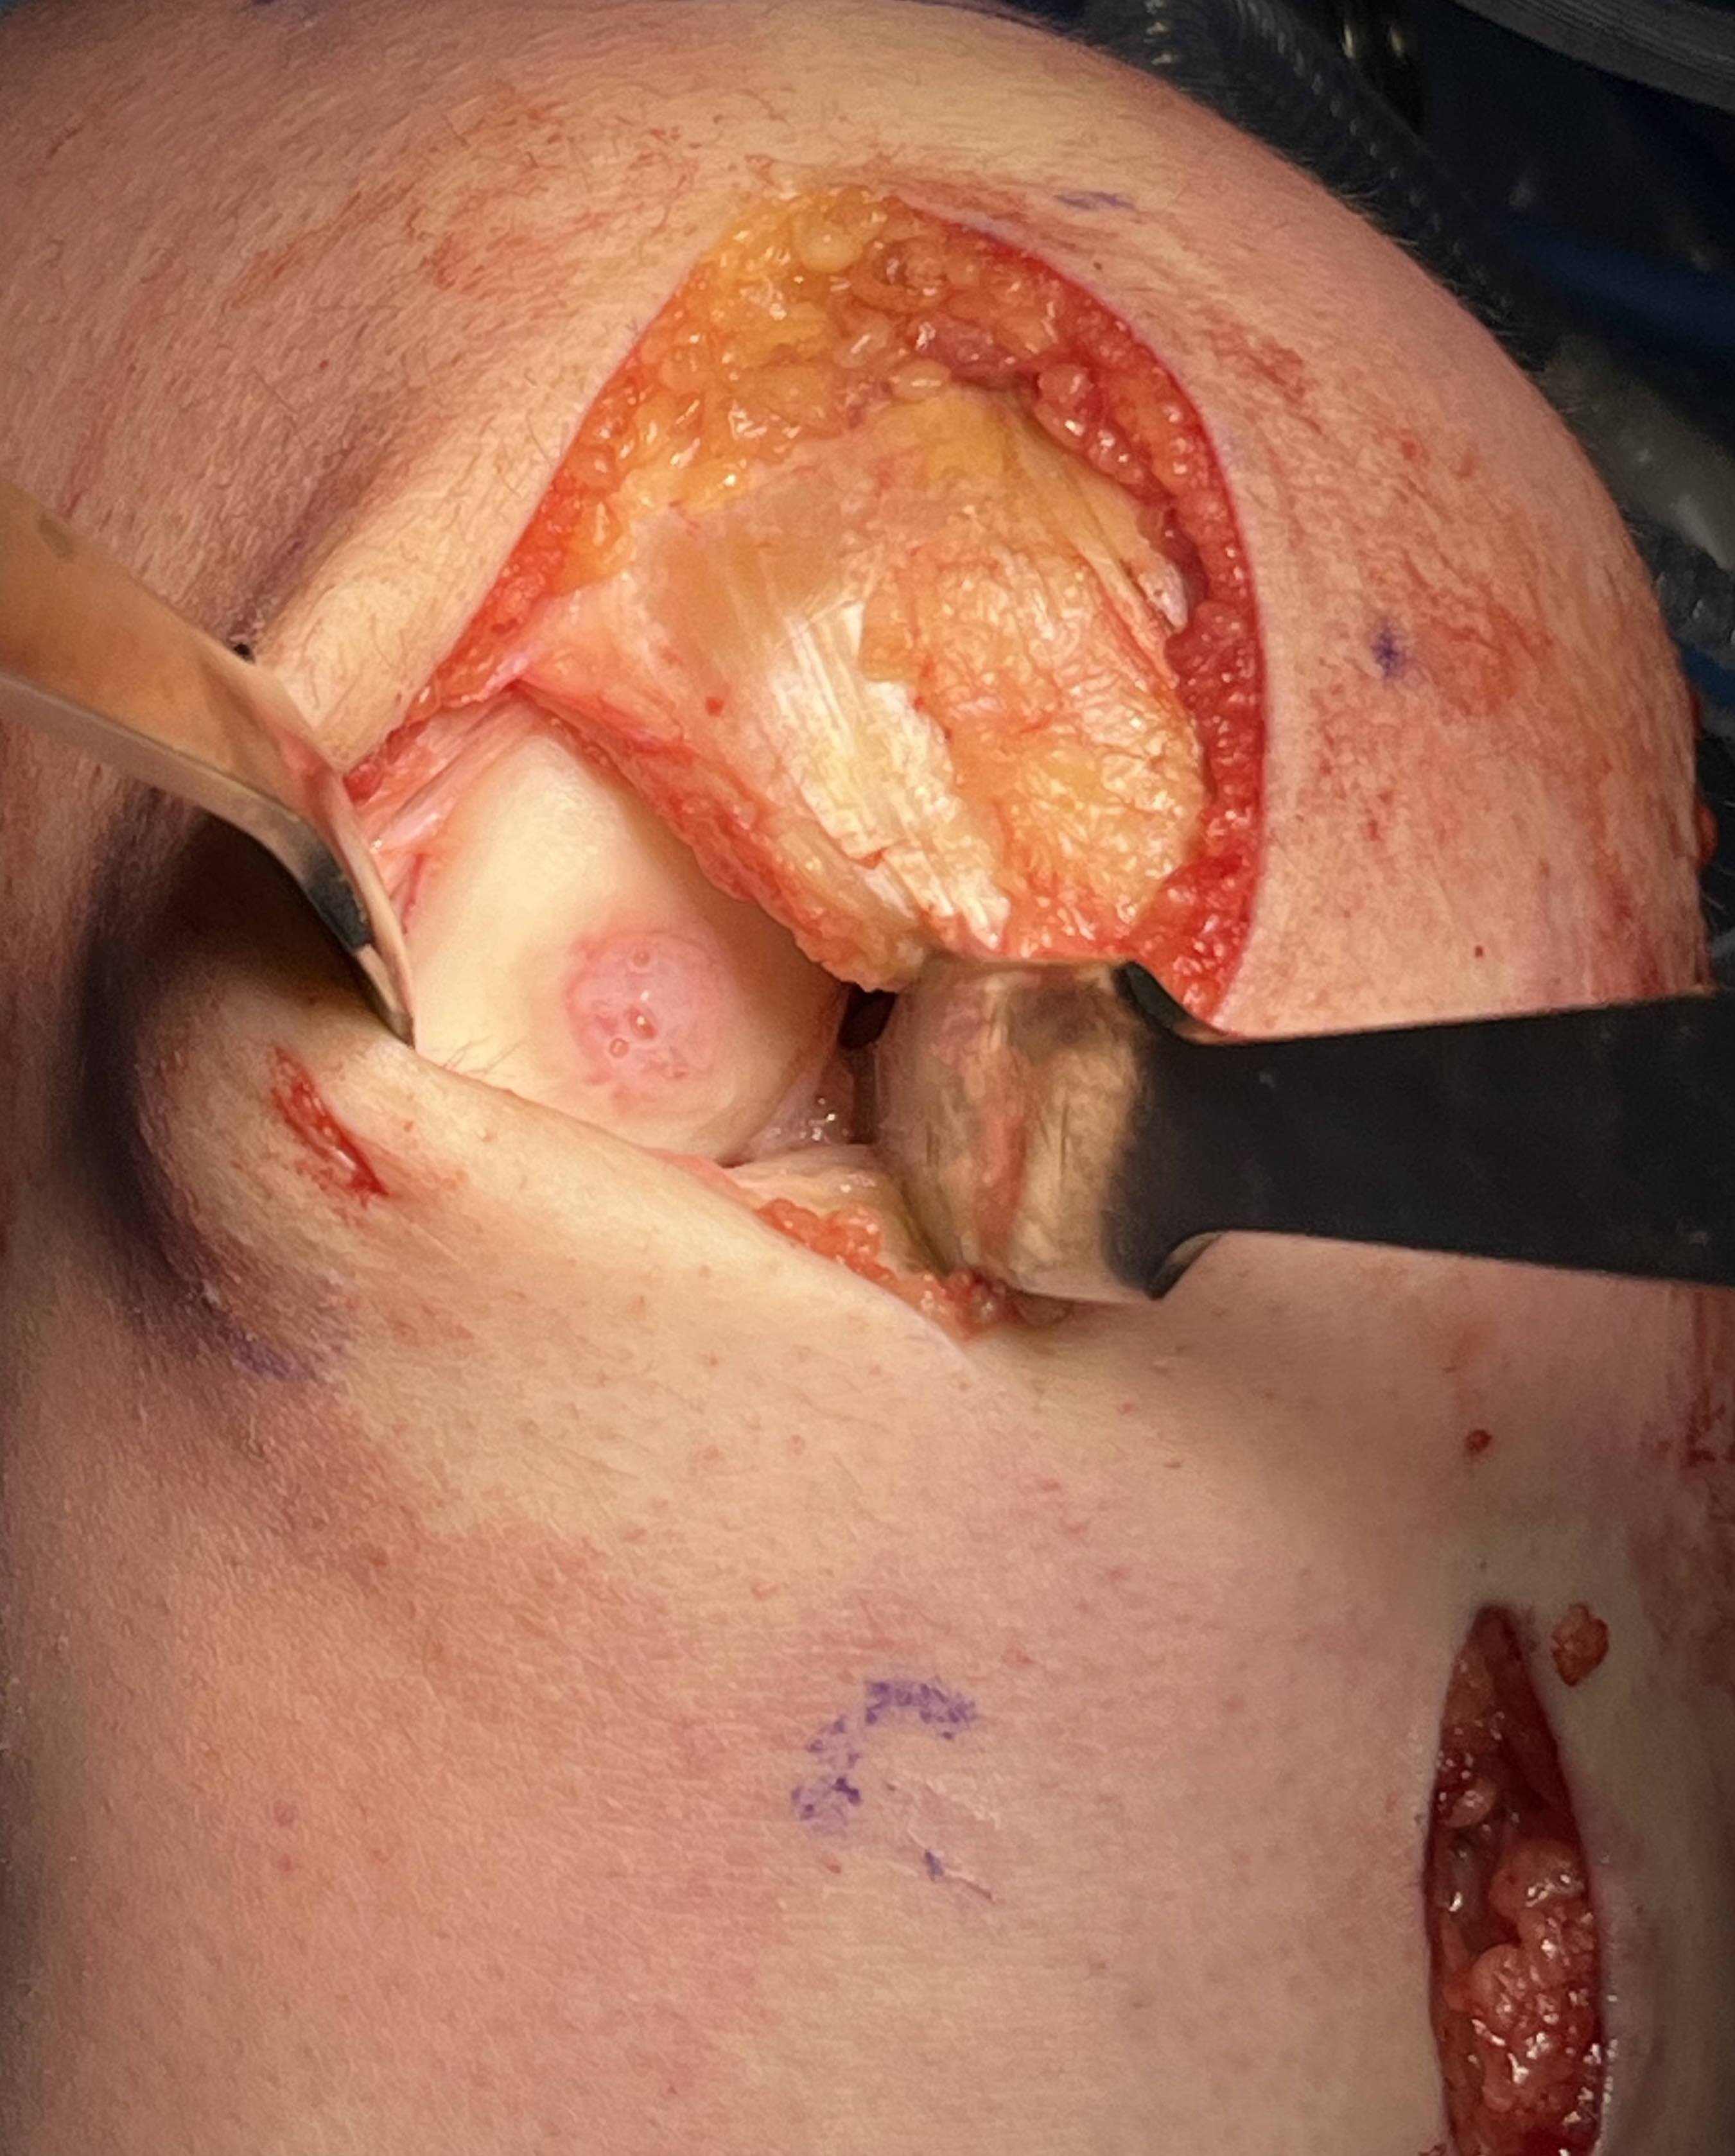

1. Dejour Trochleoplasty

- lift up anterior aspect femoral condyles

- deepening of trochlea

- replacement of LFC

- risk of chondral fracture / AVN / non union / displacement

2. Elevate lateral edge of lateral femoral condyle

- insert osteotome

- gently elevate without fracturing chondral surface

- insert 2 - 3 mm of iliac crest bone graft

- no need for stabilisation